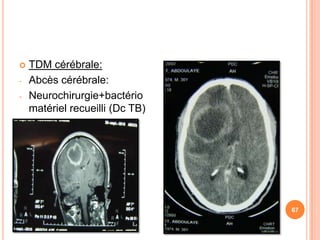

   TDM cérébrale:

-   Abcès cérébrale:

-   Neurochirurgie+bactério

matériel recueilli (Dc TB)